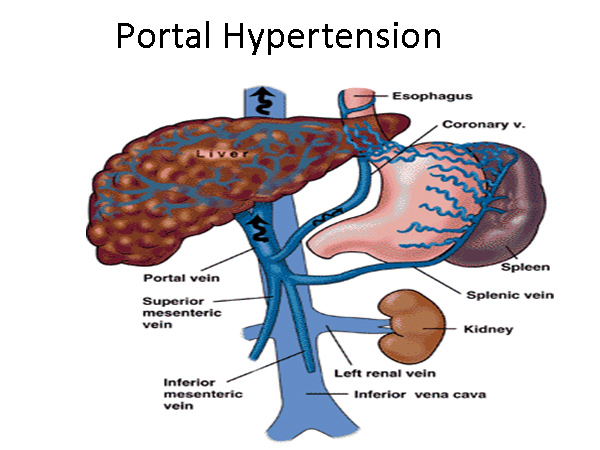

Can Hypertension Cause Portal Hypertension

Can Hypertension Cause Portal Hypertension

https://humanbodyanddiseases.weebly.com/uploads/8/0/5/9/80595380/3338075_orig.jpg

Hipertens o Portal Concise Medical Knowledge